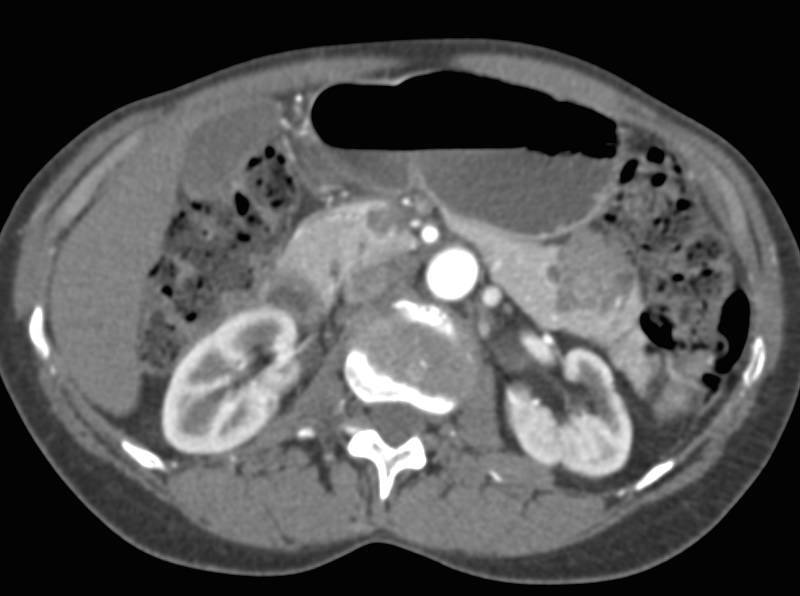

Side Branch Intraductal Papillary Mucinous Neoplasm (IPMN) in the Tail of the Pancreas